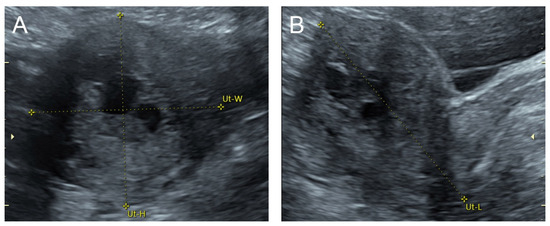

Figure 1.

(A–C) Transabdominal grayscale ultrasound: cross-sectional, sagittal, and oblique scans of the uterus showed heterogeneous soft tissue content, like pieces of conceptive product in the uterine cavity; ill-defined endometrial–myometrial interface; hypoechoic lacunae varying in size in the non-specific tissue content, mainly localized at the left anterior wall. (D) Color flow mapping with a relatively high pulse repetition frequency of 3.2 kHz (applied to the same image (C)) showed hyper-vascularized lesions in the myometrium; multidirectional flow, mainly localized at the left anterior wall; and some cystic spaces of no flow, indicating lysed blood in the cavity. (E) Spectral Doppler ultrasound showed a high peak systolic velocity (approximately 60 cm/s). The sonographic diagnosis was uterine AVM. The main differential diagnoses were incomplete abortion (conceptive products) and gestational trophoblastic disease. (F) CTA during uterine embolization revealed hypervascularity and tortuous arterial anatomy enhancing a dilated vascular pouch overlying the endometrium of the uterus with feeding via the bilateral uterine arteries and draining via the internal iliac veins, confirming uterine AVM; low blood content in the uterine cavity without evidence of active contrast extravasation.